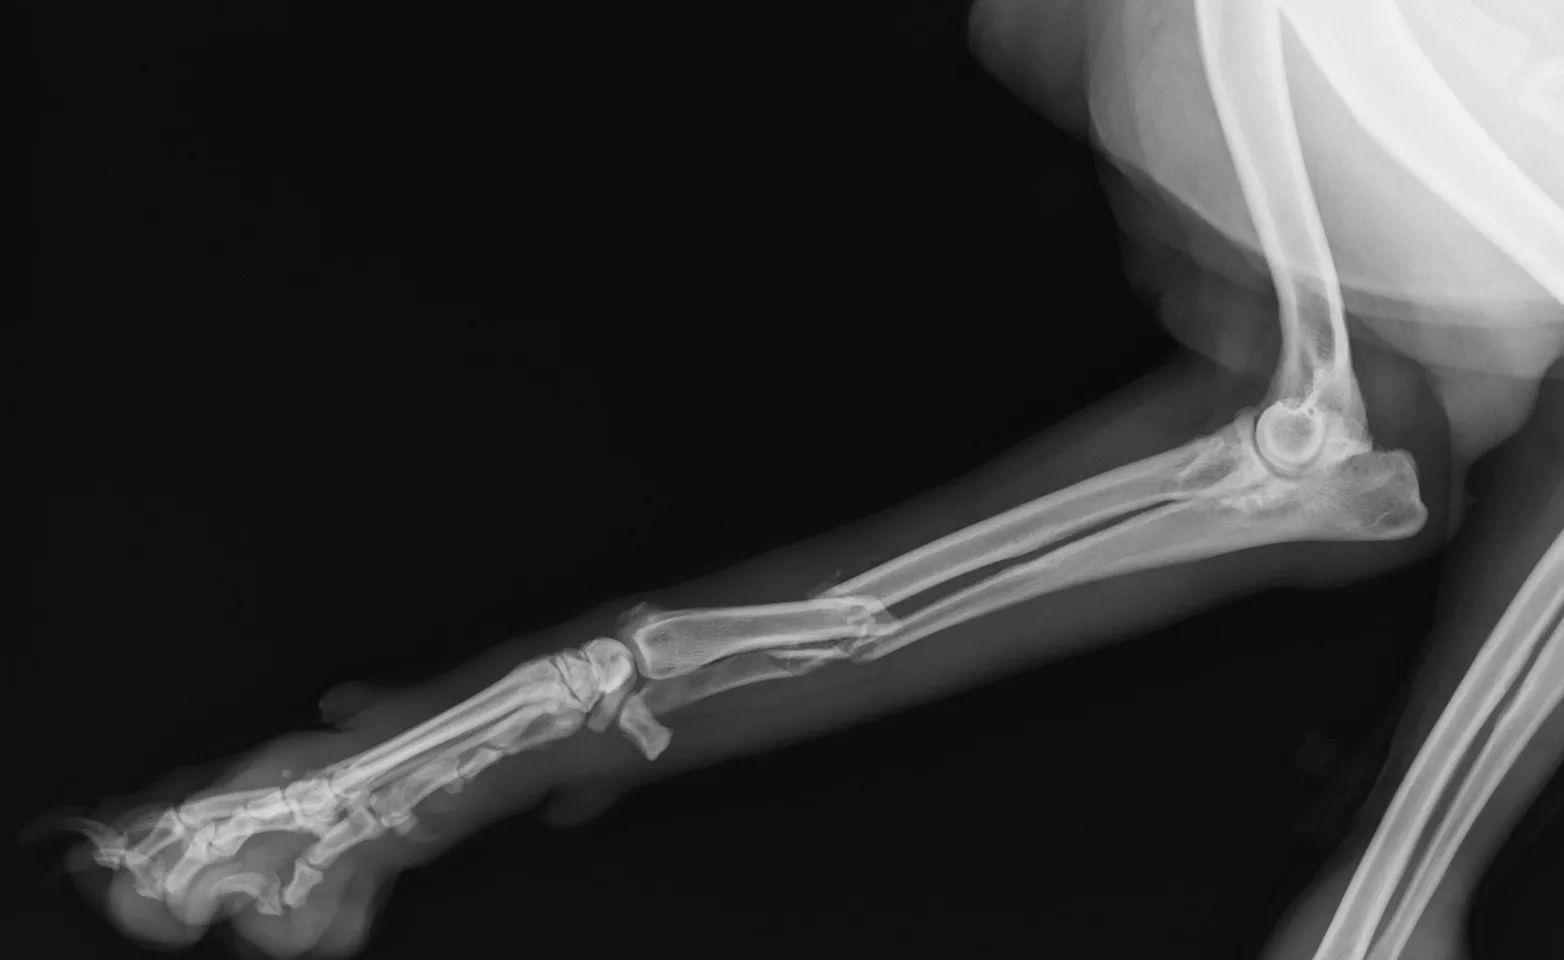

Radiography, also known as X-rays, is one of the most common and valuable medical diagnostic tools. X-rays are highly useful for screening areas of the body that have contrasting tissue densities, or when evaluating solid tissues.

X-rays can be used to detect a variety of ailments in animals including arthritis, tumors, bladder and kidney stones, and lung abnormalities such as pneumonia. They are also used to evaluate bone damage, the gastrointestinal tract, respiratory tract, genitourinary system, organ integrity, and even identify foreign objects that may have been ingested. Dental radiographs help distinguish healthy teeth from those that may need to be extracted and identify any abnormalities beneath the gums including root damage, tumours, and abscesses. In some cases, we may need to sedate your pet or use short-acting general anesthesia.